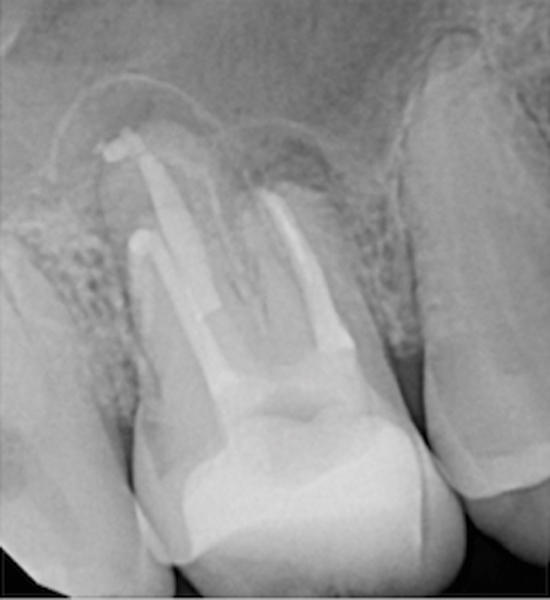

Figure 15. Preoperative radiograph. Courtesy of Dr. Sam Kratchman.

Figure 15

Figure 16. Post apicoectomy. Courtesy of Dr. Sam Kratchman.

Figure 16

Figure 17. Retropreps and isthus filled. Courtesy of Dr. Sam Kratchman.

Figure 17